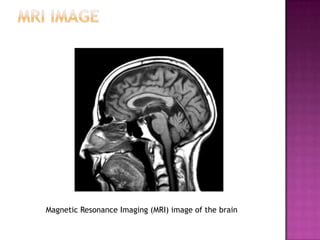

Neuroscientists use four main methods to measure brain activity and correlate it with behavior: 1) examining brain anatomy using CT or MRI scans; 2) recording brain activity during tasks using EEG, MEG, PET, or fMRI scans; 3) studying the effects of brain damage; and 4) examining the effects of stimulating specific brain areas using transcranial magnetic stimulation or injecting chemicals. However, interpreting the results of brain stimulation experiments is challenging because behaviors involve multiple brain regions.